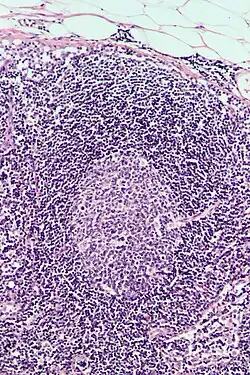

Follicular hyperplasia (FH) is a type of lymphoid hyperplasia and is classified as a lymphadenopathy, which means a disease of the lymph nodes. It is caused by a stimulation of the B cell compartment and by abnormal cell growth of secondary follicles. This typically occurs in the cortex without disrupting the lymph node capsule.[1] The follicles are pathologically polymorphous, are often contrasting and varying in size and shape.[2] Follicular hyperplasia is distinguished from follicular lymphoma in its polyclonality and lack of bcl-2 protein expression, whereas follicular lymphoma is monoclonal, and expresses bcl-2.[3]

Follicular hyperplasia can be distinguished among other diseases by observing the density of a lymph follicle on low magnification. Lymph nodes with reactive follicles contain extensions outside its capsule, follicles present throughout the entire node, obvious centroblasts and the absence or diminishing mantle zones. Immunohistochemistry can help distinguish a difference between a patient with follicular lymphoma to follicular hyperplasia.[1] Reactive follicular hyperplasia does not express BCL2 proteins in B cell germinal centers and are absent light chain reaction in immunostaining and flow cytometry as well as absent IG rearrangements.[1]

BCL2 protein expression is usually absent in follicular hyperplasia but prominent in follicular lymphomas. A comparison with other stains that include germinal center markers such as BCL-6 or CD10 is useful to compare when determining a proper diagnosis.[1] CD10 positive cells are metalloproteinase which activate or deactivate peptides through proteolytic cleavage.[9]